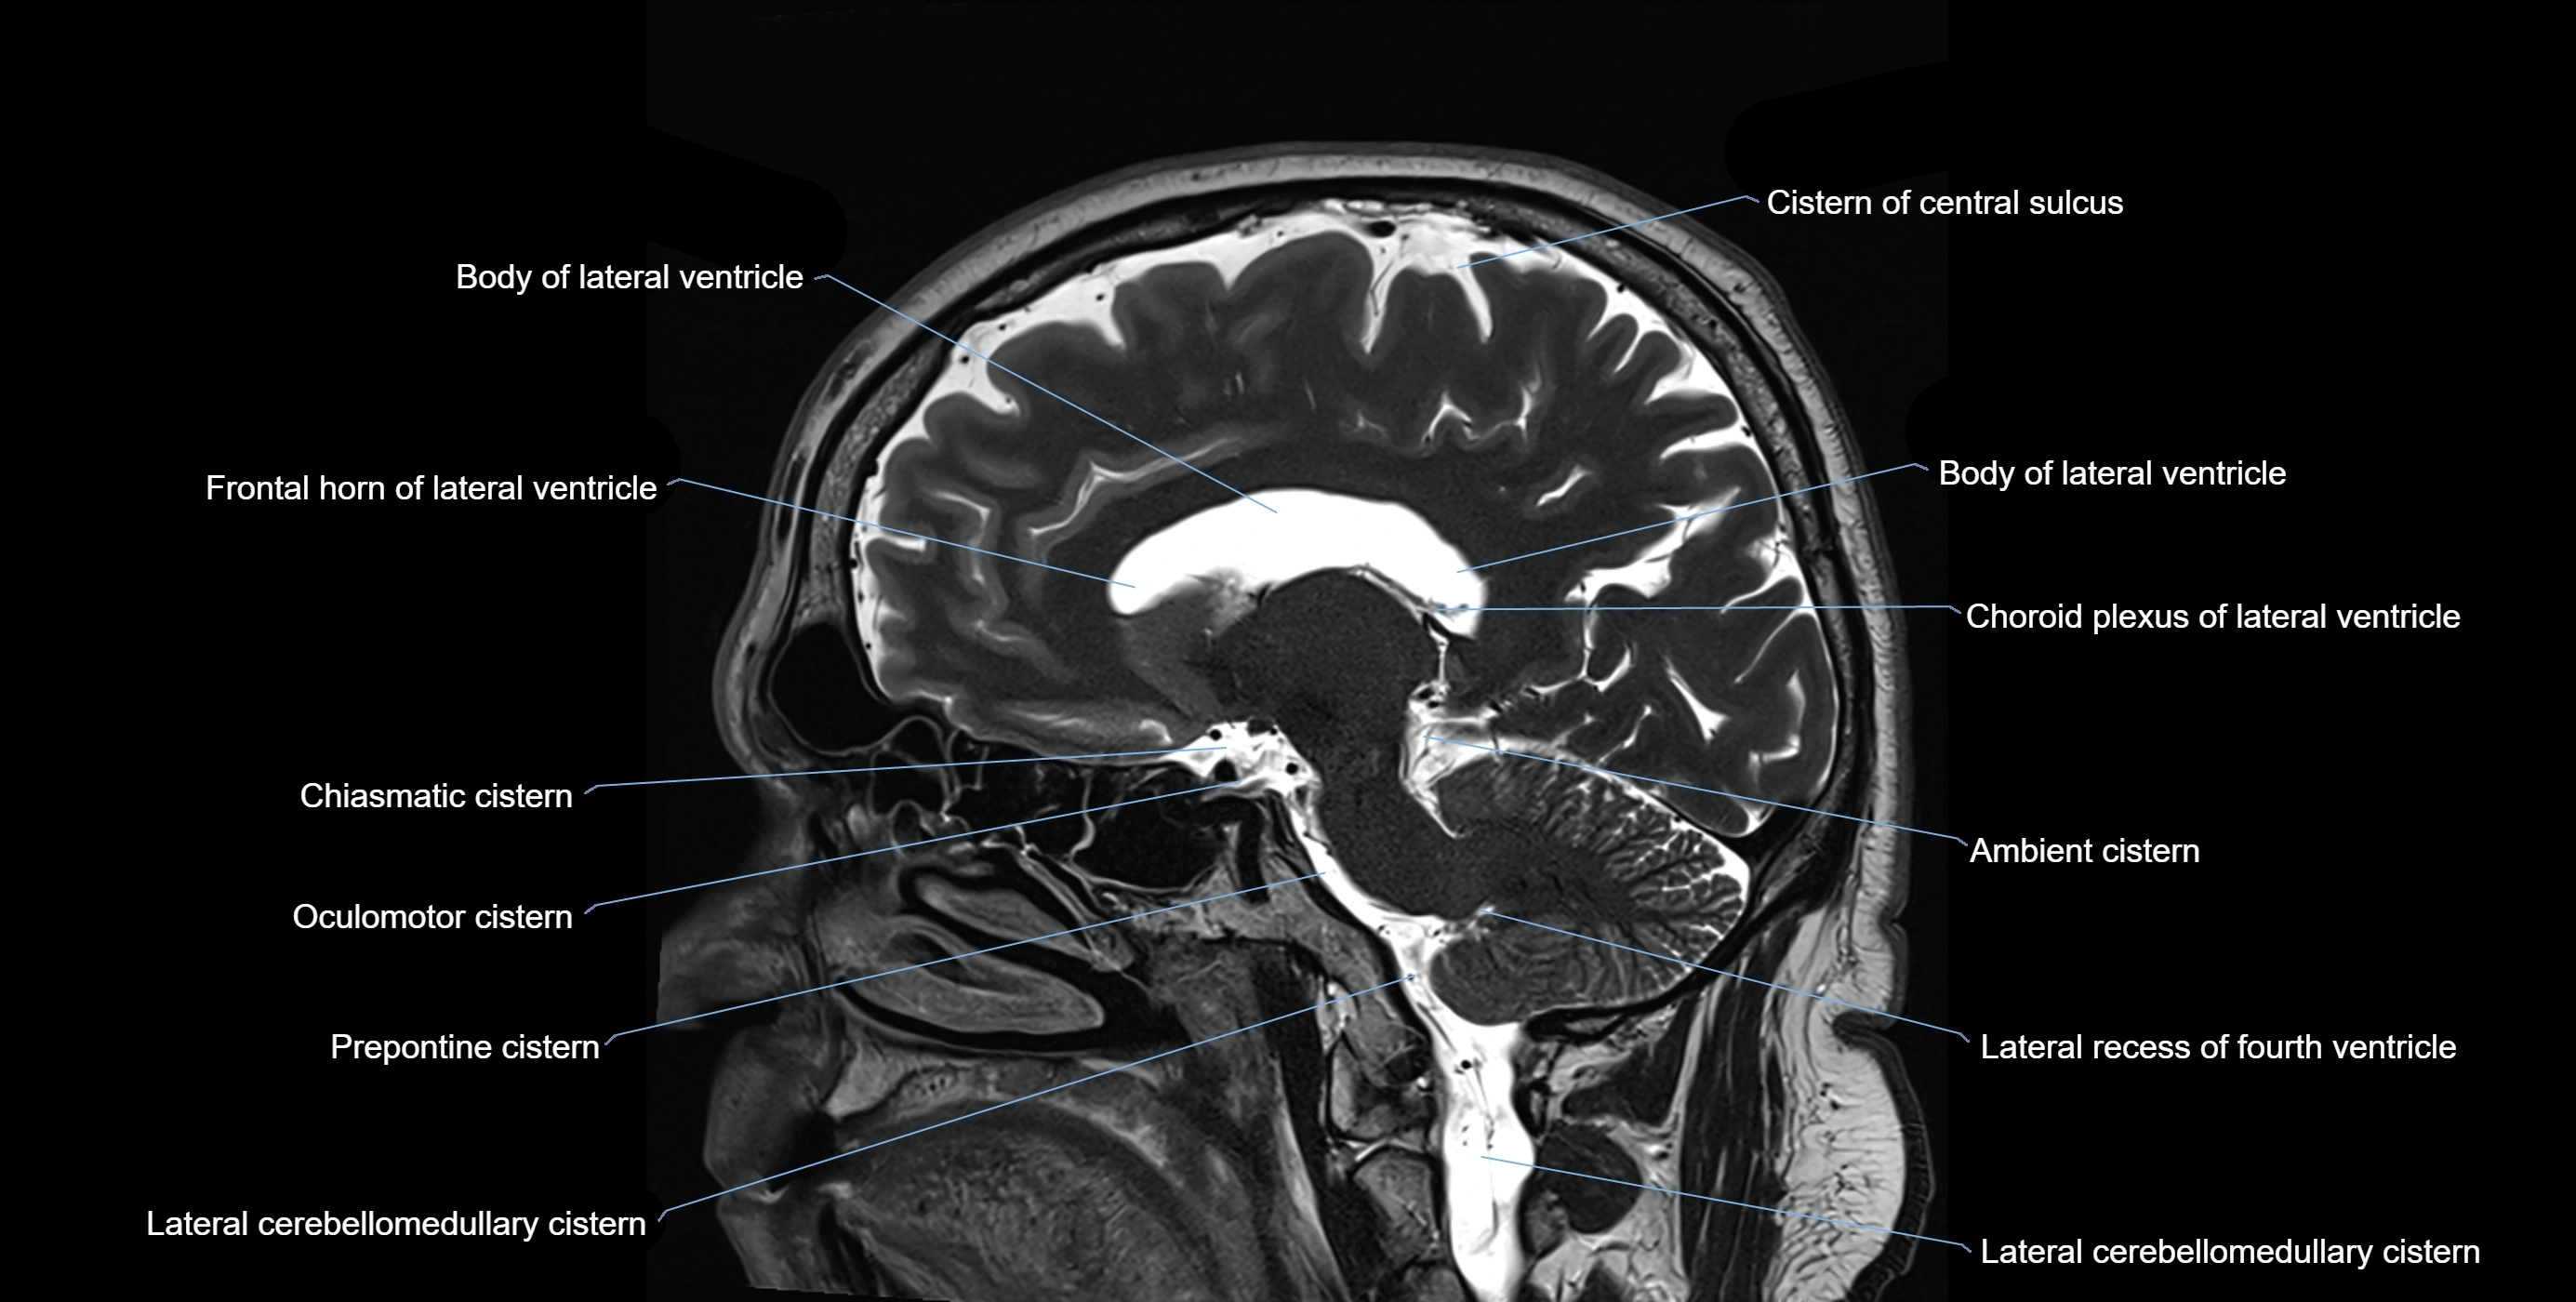

MRI images

image